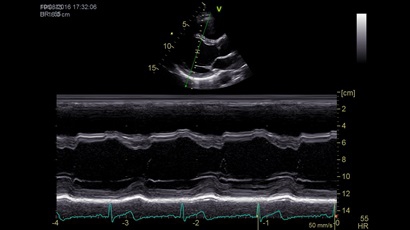

GE VIVID IQ - это передовая портативная система ультразвуковой диагностики, специально разработанная для обеспечения высокого качества образов и мобильности. Благодаря своим компактным размерам и легкому весу, VIVID IQ легко переносится и позволяет проводить УЗИ исследования в различных местах, включая комнаты пациентов, отделения скорой помощи и операционные.

GE VIVID IQ – это ультрасовременный, выполненный в виде ноутбука УЗИ сканер с самым передовым техническим оснащением для проведения диагностических обследований сердечно-сосудистой системы человека. Его особенно оценят бригады скорой помощи из-за малого веса всего 4,5 кг., удобства переноски, а также быстрого выхода из состояния сна для начала работ.

• Передовые технологии, такие как 4D чреспищеводная эхокардиография, ЭКГ, стресс-эхо, внутрисердечная ультразвуковая эхокардиография, тканевый доплер и другие.

Анатомический М-режим:

Да

M-режим:

• Режимы: 4D, 2D (B-режим), цветной допплеровский режим, режим энергетического допплера, M-режим, цветной M-режим, спектральные режимы импульсно-волнового допплера (PW) и непрерывно-волнового допплера (CW), визуализация скорости движения тканей.